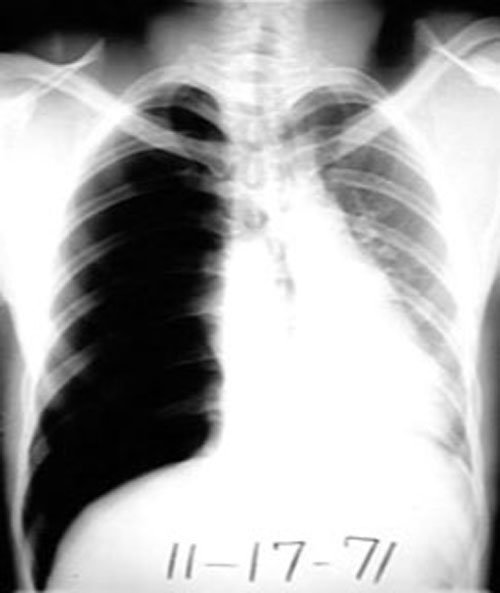

Note the shift of mediastinum to left.